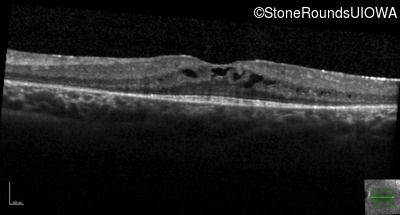

Optical Coherence Tomography - Left - 20/50

Exemplar / OCT Stack